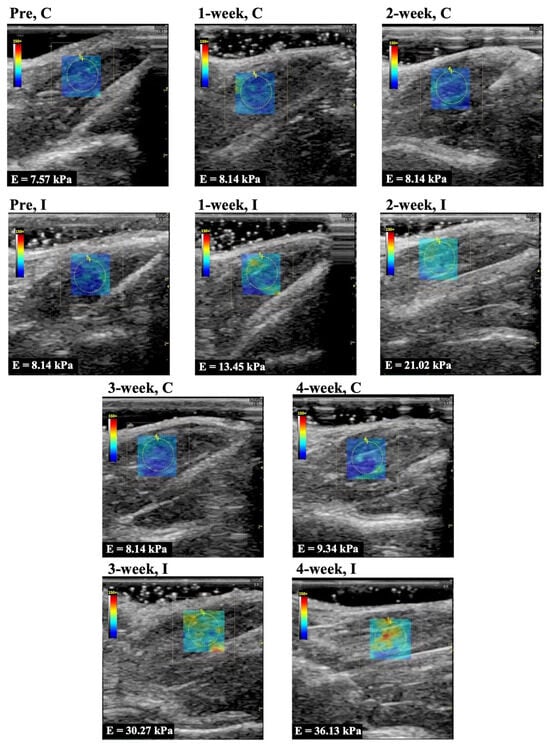

Representative longitudinal ultrasound shear wave elastography images of the rectus femoris, vastus lateralis, and vastus medialis muscle are shown in Figure 2, Figure 3, and Figure 4, respectively. In Group I, cyan, orange, and red colors increased during the immobilization period, suggesting an increased elastic modulus.

The elastic modulus of the rectus femoris, vastus lateralis, and vastus medialis muscle as determined by ultrasound shear wave elastography are shown in Figure 5A–C. The elastic modulus of the rectus femoris, vastus lateralis, and vastus medialis muscles in Group C were 8.6 ± 1.0, 7.4 ± 1.3, 7.6 ± 1.1 kPa (mean and standard deviation) in before experiment, 7.5 ± 1.4, 7.8 ± 0.8, 8.7 ± 0.5 kPa in 1 week, 7.4 ± 1.2, 7.1 ± 1.6, 8.0 ± 1.5 kPa in 2 weeks, 8.6 ± 1.2, 7.5 ± 0.9, 8.4 ± 0.7 kPa in 3 weeks, and 8.0 ± 1.0, 7.4 ± 1.0, 8.5 ± 0.7 kPa in 4 weeks, respectively. The elastic modulus of those muscles in Group I was 8.3 ± 1.2, 7.4 ± 1.1, 7.7 ± 1.1 kPa in the before experiment, 15.0 ± 1.4, 15.2 ± 2.2, 14.5 ± 1.5 kPa in 1 week, 20.1 ± 1.7, 19.6 ± 2.2, 18.9 ± 2.5 kPa in 2 weeks, 29.0 ± 2.1, 28.8 ± 1.7, 29.2 ± 2.4 kPa in 3 weeks, and 30.6 ± 2.7, 32.9 ± 4.0, 33.1 ± 3.4 kPa in 4 weeks, respectively. The elastic modulus for all periods in Group I was significantly higher (p = 0.0001 in all muscles) compared with the same periods in Group C. In Group I, the elastic modulus increased after more than 3 weeks of immobilization compared to the 1 and 2 week immobilizations.

Figure 3. Representative shear wave elastography of the vastus lateralis muscle. C, control group; I, immobilization group; Pre, before the experiment; E, elastic modulus. The rectangle indicates the region of interest. The measurement circle was 2 mm in diameter.